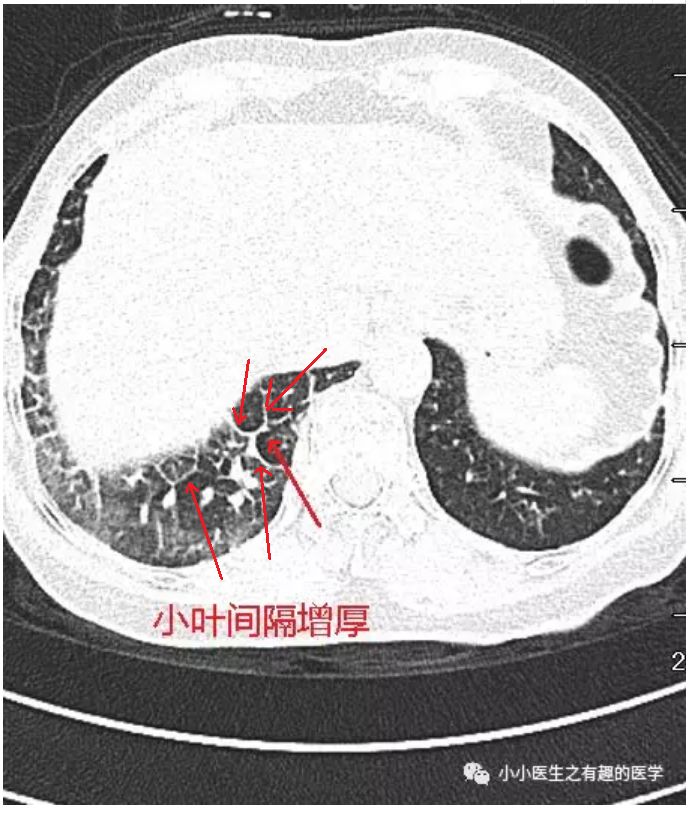

比较大的间隔增厚,是小叶间隔增厚,如下图:

图4